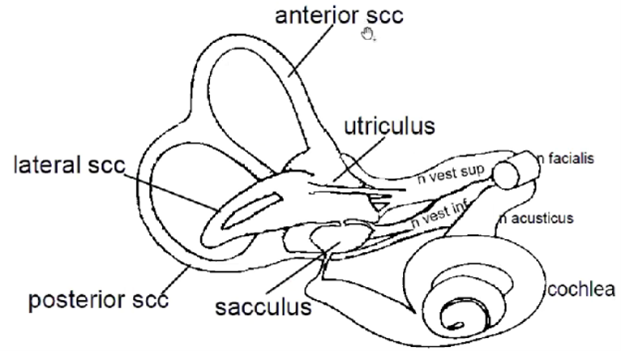

- SCC – semi cirkular canal (båggång)

Vad ansvara de olika delarna för?

- SCC – semi cirkular canal (båggång)

- Anterior (rörelser framåt snett)

- Posterior (rörelser bakåt snett)

- Lateral (huvud fram och tillbaka horisontalt)

- Cochlea ger info till n. acusticus

- Balanssystem består av tre båggångar som ger information till

- övre vestibularisnerv – anterior scc, lateral scc och utriculus

- nedre vestibularisnerv – posterior scc och sacculus

- Ovan tre nerver går ihop till n. vestibulocochlearis och sällskapar sen med n. fascialis

Temporal fraktur kan ge problem med vad med tanke på vilke nerver som löper där?

Balans (vestibulär del), hörsel och muskler i ansikte